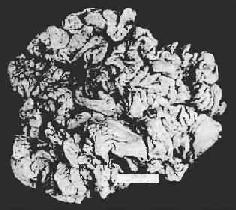

巨肥厚性胃炎Ménétriér病的特點是胃體黏膜皺襞巨大扭曲像腦回,是表層和腺體的粘液細胞增生所致,使胃小凹延長扭曲,在深處有囊樣擴張並伴有壁細胞和主稀少的減少。胃竇一般正常。如在肥厚黏膜上發生潰瘍,可按胃潰瘍處理。蛋白質丟失如持續而加重,可能需要全胃切除。

1、X線檢查:皺襞巨大屈曲,大彎側常有息肉樣改變,皺襞不如正常的清晰和柔軟。蠕動波減少,運動緩慢。127例中有60%懷疑有惡性病變。

2、胃鏡檢查:可見巨大皺襞充氣後不消失,蒼白如棒狀。黏液特多。皺襞表面不規則,常呈大小不等結節樣或息肉樣。皺襞間有深的裂隙。表面顏色可以蒼白、灰色或紅色健康搜尋。總之胃鏡診斷也不太容易:①不易考慮到本病;②不易鑑別。